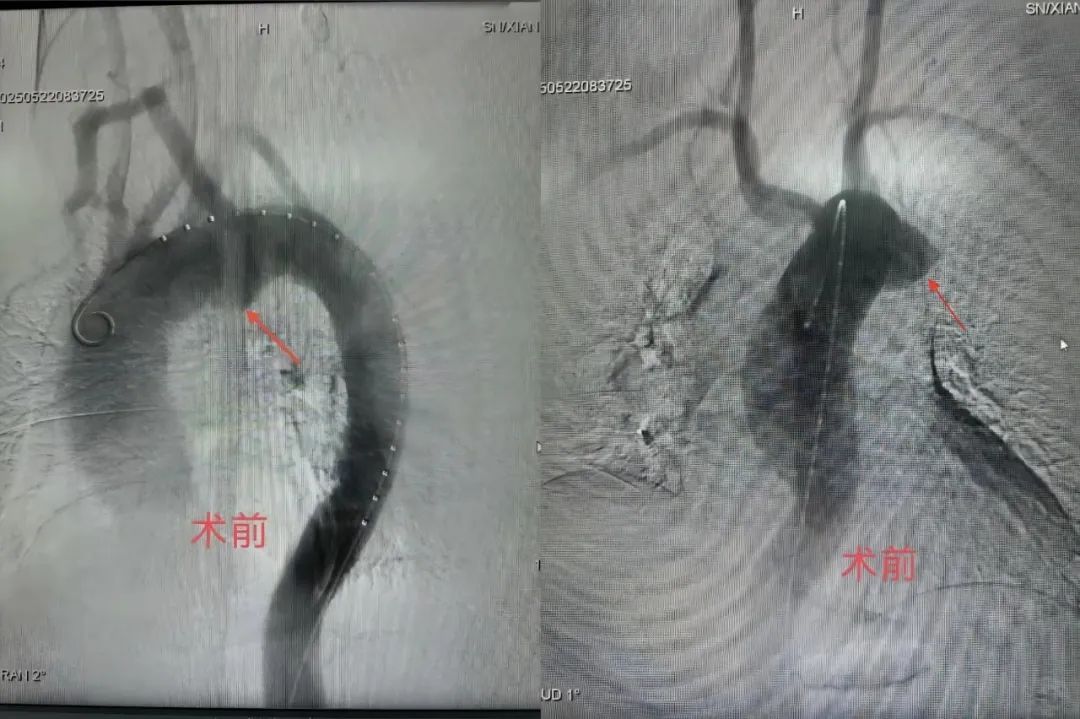

(术前造影)

患者朱先生(化名)因“咳嗽、咳痰”于外院查胸部CT时发现主动脉弓旁见鹿角样凸起,与主动脉弓分界不清,进一步行增强CT后考虑假性动脉瘤并血栓形成,主动脉管壁多发不规则溃疡。入我科治疗时考虑患者胸主动脉假性动脉瘤随时有破裂出血致死可能。并且患者主动脉弓弓形复杂,右锁骨下动脉发自于左锁骨下动脉左侧,主动脉弓后方,按照常规主动脉覆膜支架置入术进行手术会造成后循环严重缺血,甚至有致死、致残可能。

经血管介入科团队深入研究患者解剖特异性,精心设计手术方式,反复推演手术过程,最终决定采用国内前沿的“双开窗”技术。术前经过缜密测量,准确定位,预先在胸主动脉主体支架上行体外开窗,将开窗口置于迷走的右锁骨下动脉开口处保证一侧大脑后循环血供,然后打开主体支架,最后通过体内开窗技术,成功开通左锁骨下动脉并置入分支支架。